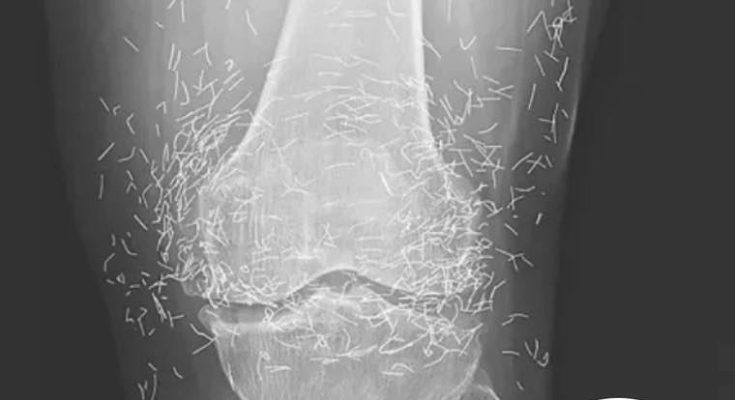

A 65-year-old woman in South Korea experienced a shocking medical discovery when doctors found hundreds of tiny gold needles embedded in her knee tissue during a routine X-ray. She had been suffering from chronic osteoarthritis, a condition that causes joint pain, stiffness, and inflammation due to cartilage breakdown.

In this case, the needles were intentionally left in her body as part of a long-term treatment strategy. Some practitioners believe that leaving gold needles or threads in place can provide ongoing stimulation to the affected area. However, medical professionals warn that this approach carries significant risks.

Dr. Ali Guermazi, a radiology expert from Boston University not involved in the case, explained that the human body can react negatively to foreign objects. Inflammatory responses, tissue damage, and infections are potential complications. Additionally, the embedded needles can interfere with medical imaging, making diagnosis more difficult.

One of the most serious risks comes with MRI scans. The powerful magnetic forces used in MRIs can cause metal objects to move within the body, possibly leading to punctured blood vessels or other life-threatening injuries. This makes metal implants a critical concern for patients who may need future imaging.